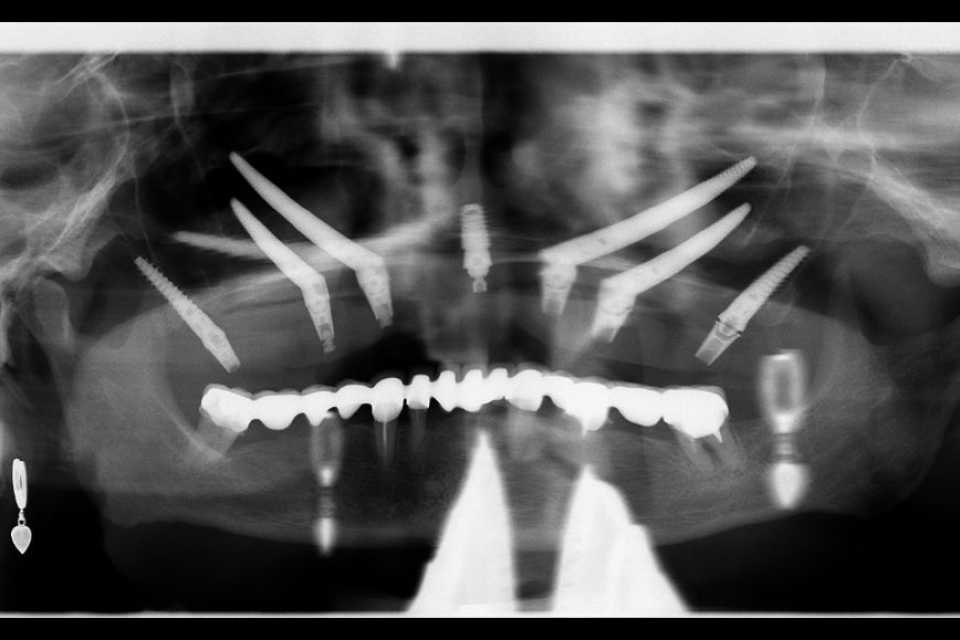

Pentru a răspunde nevoilor sale, s-a optat pentru utilizarea unor implanturi orale speciale: 4 implanturi zigomatice, 2 implanturi pterigoide și 1 implant standard. Această abordare a permis reabilitarea completă a arcadei dentare superioare printr-o lucrare protetică fixă, înșurubabilă, realizată din ceramică pe suport de zirconiu.